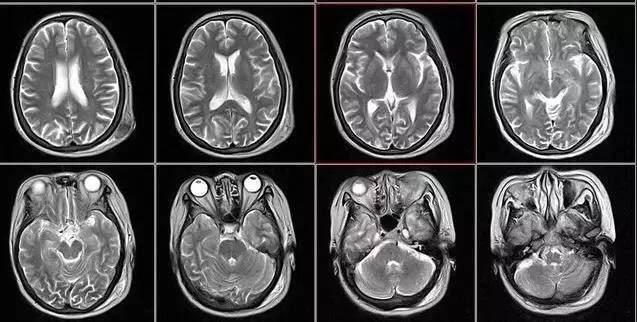

核磁共振:摇一摇再看

核磁共振机使用较强大的磁场,使人体中所有水分子磁场的磁力线方向一致,这时磁共振机的磁场突然消失,身体中水分子的磁力线方向,突然恢复到原来随意排列的状态。简单说就相当于用手摇一摇,让水分子振动起来,再平静下来,感受一下里面的振动。所以,核磁共振(MRI)也被戏说为是摇摇看的检查。

2、颈椎腰椎——最佳选核磁、次选CT

颈椎病、腰椎间盘突出等椎间盘疾病需要观察椎间盘与相应的神经根,要想更好观察这些软组织,最优选择就是核磁。同样,对于关节、肌肉、脂肪组织检查,核磁也是首选。